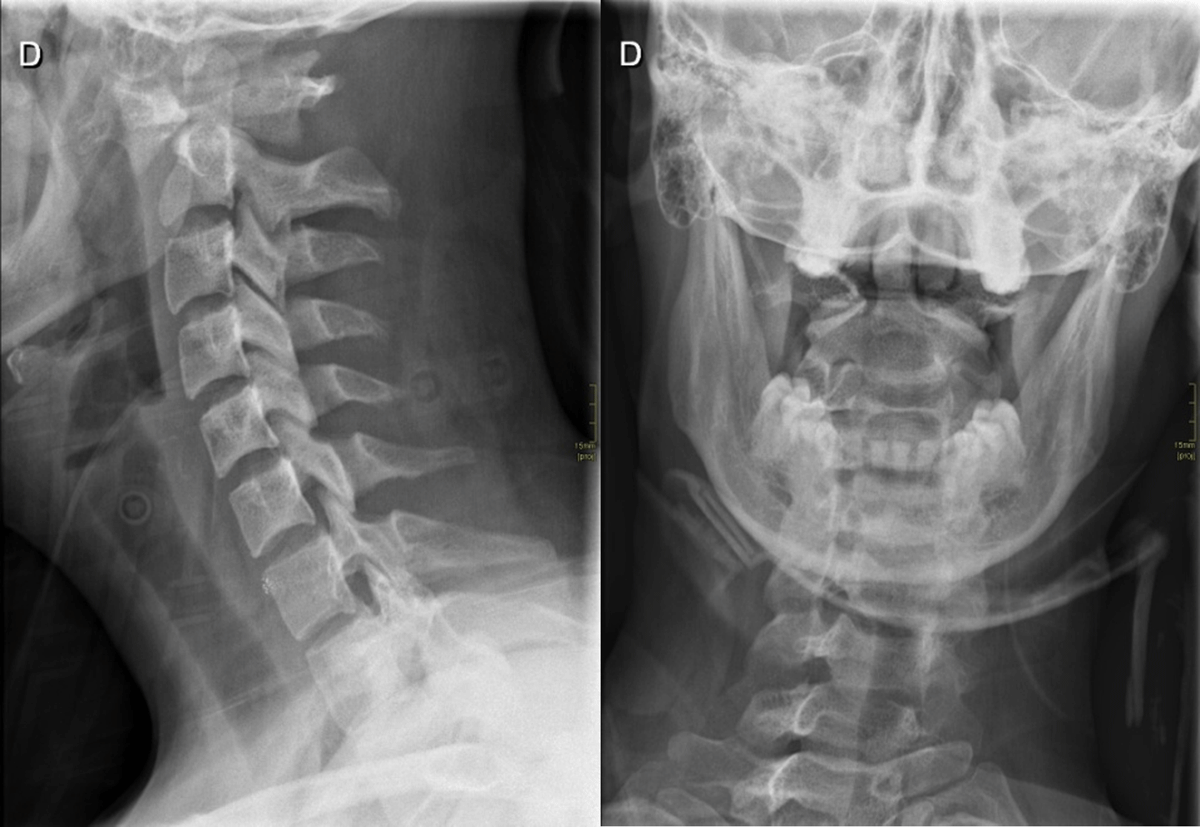

Figure 3

Lateral and open mouth views radiographs.